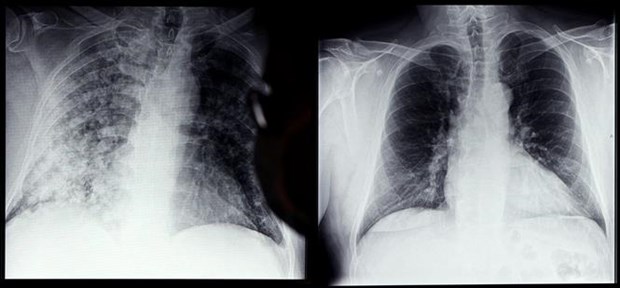

- Đã tìm ra lý do COVID-19 gây tổn thương kéo dài trong cơ thể